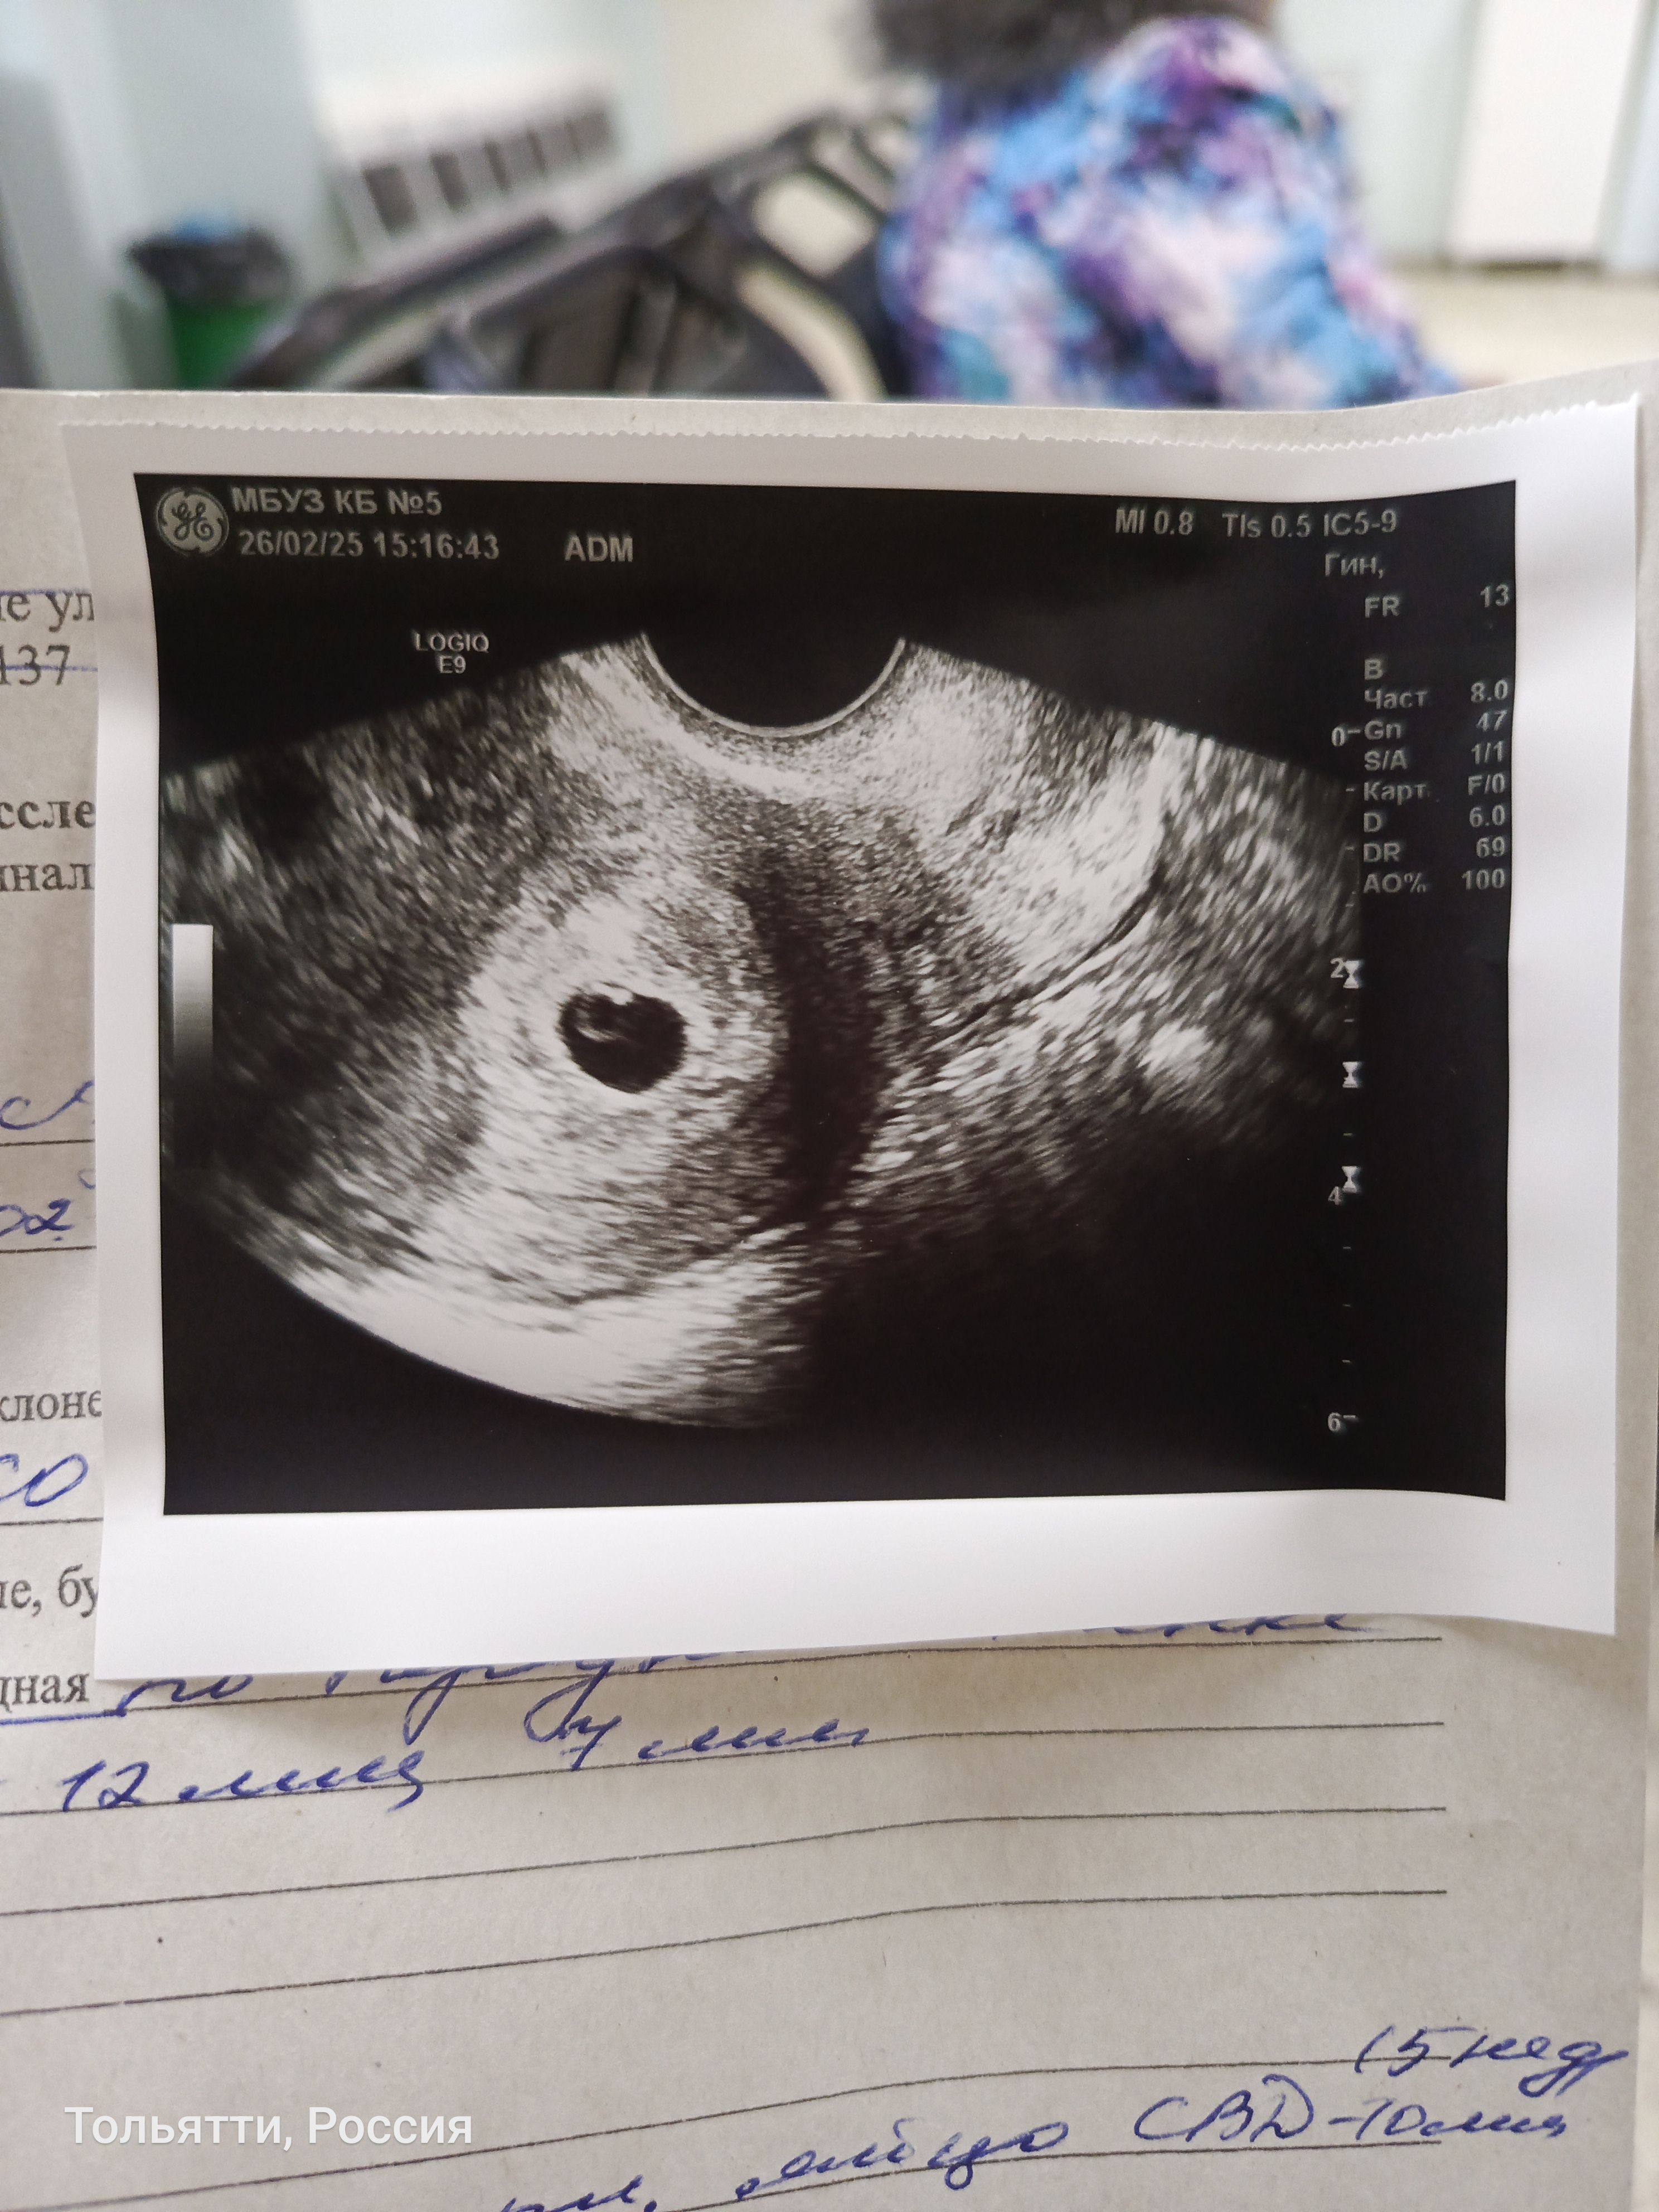

21 дпп и наше первое узи

Сказали все отлично...сердечко и эмбриончик пока толком не видно...Поставили 5 неделек...следующее УЗИ аж 7 марта ...дождаться бы🙏